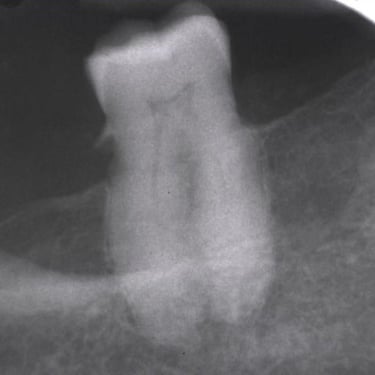

Hipercementosis

La hipercementosis es un engrosamiento anormal del cemento radicular del diente, a menudo debido a una inflamación crónica o trauma.

Los pacientes generalmente no tienen síntomas, pero la condición puede ser descubierta en una radiografía.

El tratamiento no suele ser necesario a menos que cause problemas con la extracción del diente.